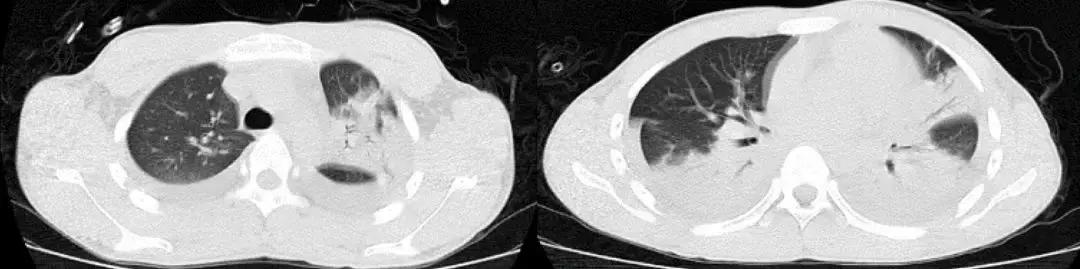

1天前急救车于我院急诊,血常规提示白细胞明显升高,胸部CT(2017-3-15):两肺感染,右肺上叶中叶膨胀不全,两肺间质改变,两肺肺气肿;急诊给予「头孢哌酮舒巴坦联合万古霉素」抗感染治疗,面罩10L/分吸氧维持血氧饱和度在85~95%之间,现为进一步诊治以「重症肺炎」收住我科。

CT:2018-3-15

既往有高血压病,患高血压10余年,平日未监测血压,最高达170/100mmHg,未规律服用降压药,血压控制差。2年前诊断结肠癌,行手术治疗,术后化疗6个疗程(具体用药不详),结肠癌术后逐渐出现活动后呼吸困难,并进行性加重,未诊治。吸烟40余年,1~2包/日,戒烟2年;家族史无特殊。